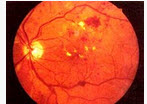

经济发达地区盲的主要原因是()

A:青光眼

B:白内障

C:沙眼

D:糖尿病性视网膜病变

E:角膜病